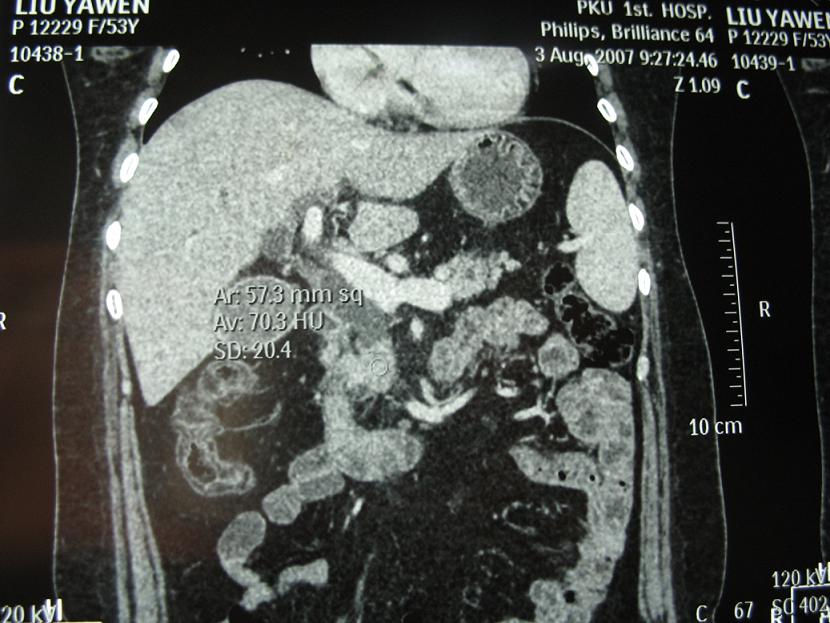

标题: CT17151:女 53岁 腹痛数月余 轻微黄疸 [打印本页]

女 53岁 腹痛数月余 轻微黄疸

1)考虑胰头癌。2)胆囊炎。

壶腹周围占位(钩突ca?)

胰腺钩突mt

支持胰腺钩突ca伴胆系梗阻,胆囊炎

考虑 胰头癌可能性大。